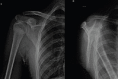

Case report: We have included five cases of osteochondromas occurring at rare locations with variable presentations and their management. We have included one case of metacarpal, one case of skull exostosis, two cases of scapula exostosis, and one case of fibula exostosis.